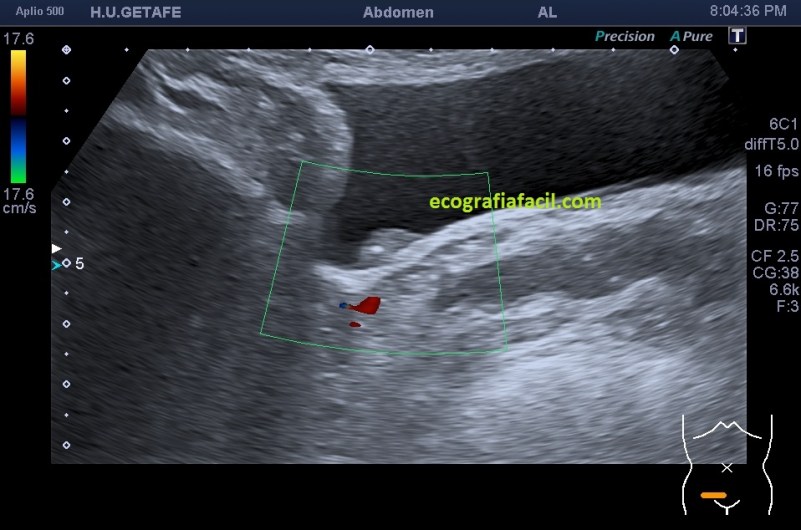

La imagen 2,3,4 y 5 demuestran una lesión de pared vesical, ovalada, hiperecogénica, muy pequeña, con un calcio en su interior (flecha amarilla), pequeña para poder demostrar vascularización, sospecha en el informe de tumor maligno de vejiga, el paciente entra en circuito de neoplasia precoz. A las pocas semanas fue operado, no hizo falta quitarle la vejiga. La detección fue en este caso, vital.

En este tipo de lesiones, si conseguimos demostrar vascularización, es diagnóstico confirmado de Urotelioma.